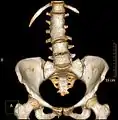

تكتل فقرات خلقي في العمود الفقري القطني. تقديم حجم أشعة مقطعية.